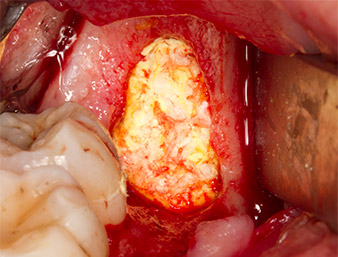

Das Gewebe über dem Wurzelrest war nicht vollständig verknöchert und bestand zu einem großen Teil aus entzündlich verändertem Granulationsgewebe (Abb. 4).

Um autogenes Material für die spätere Wundversorgung zu gewinnen, wurden mit einem piezochirugischen Instrument (Piezomed B5) gesunde Knochenspäne aus der Umgebung des Wurzelrests gewonnen (Abb. 5).